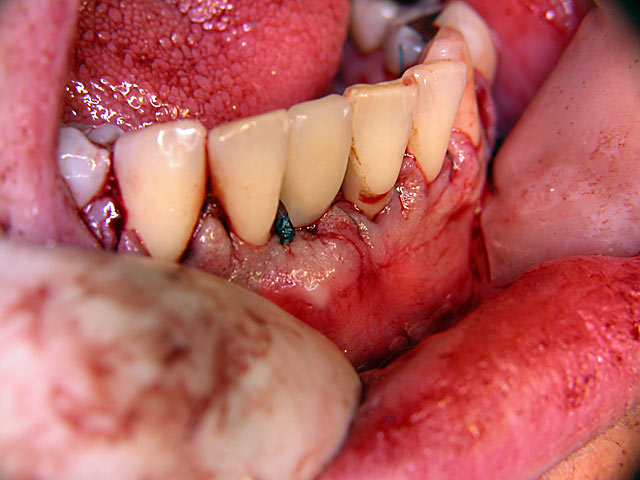

Die folgenden Patientenfälle sollen Ihnen einen Einblick in die Möglichkeiten der modernen Implantation geben.